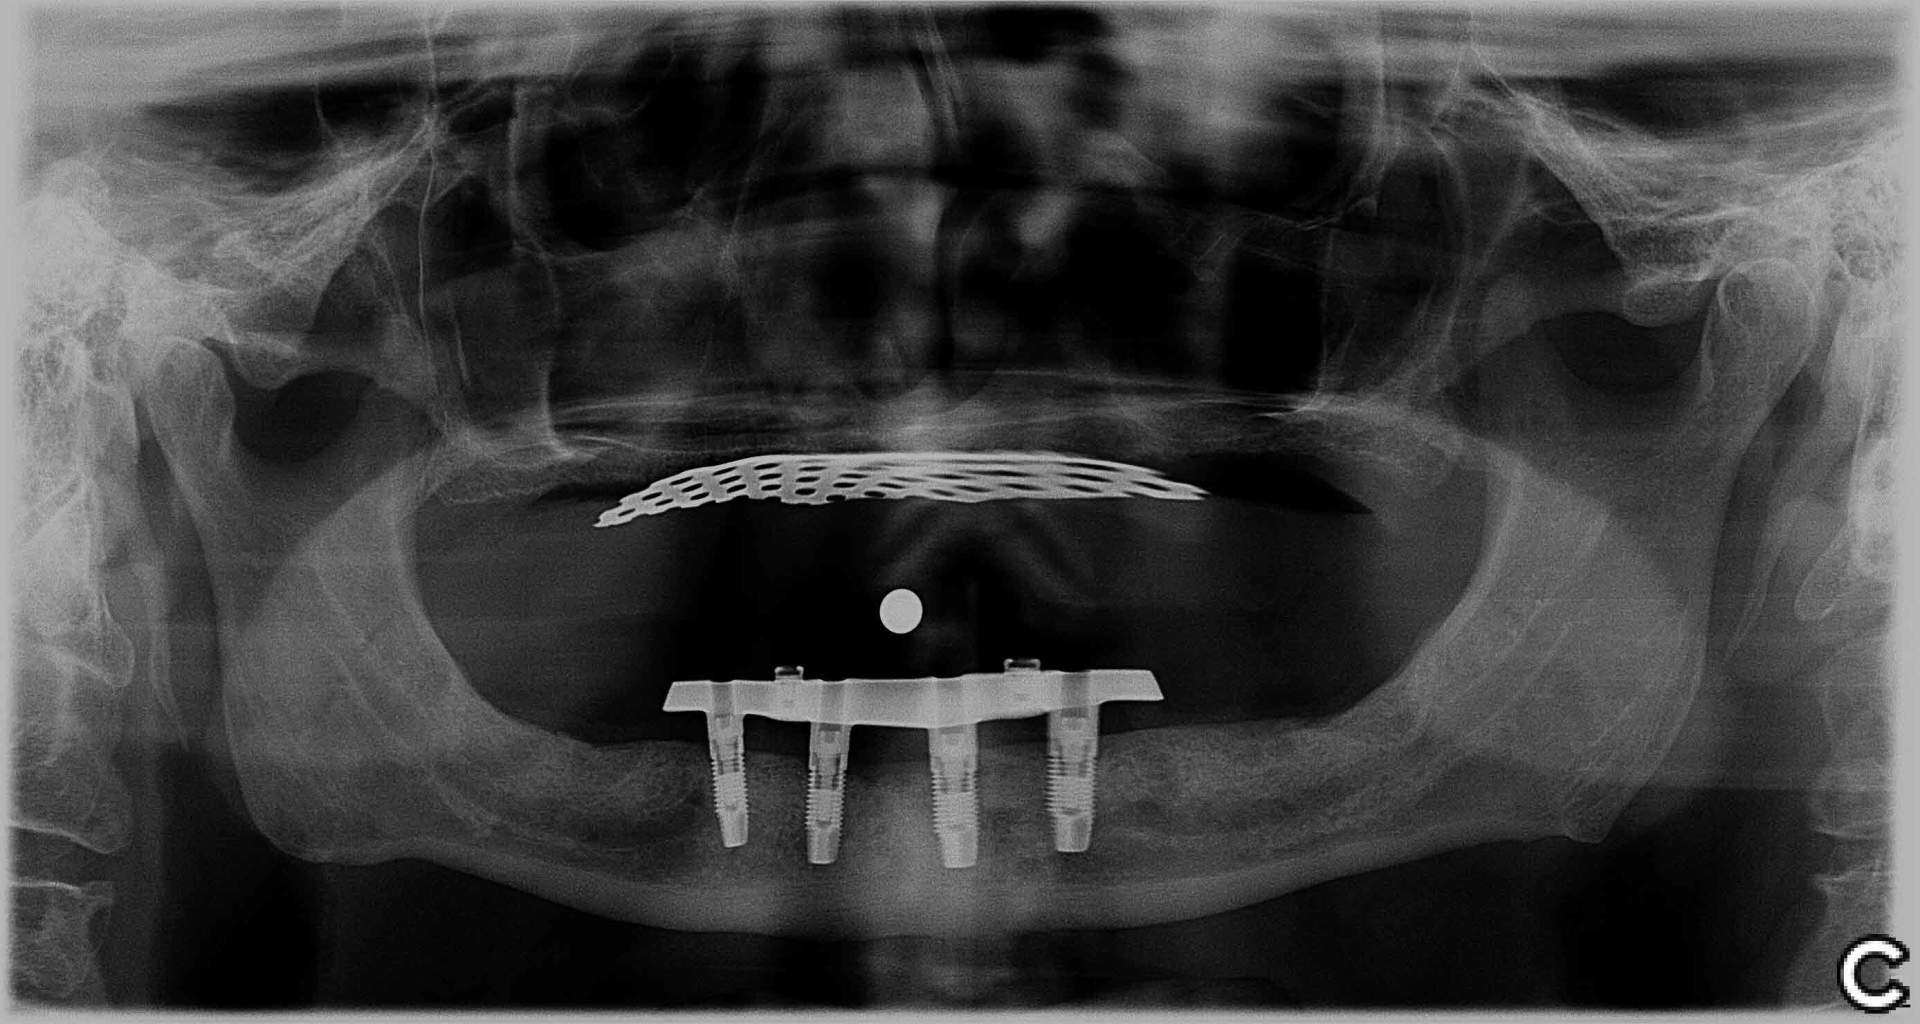

“I first met with Dr. Anh Nguyen in November 2008. With a transplant bone in my right lower jaw, crafting new dentures was a complicated procedure. Dr. Anh Worked with efficiency and compassion - a wonderful combination. During the entire process, she always demonstrated concern for my comfort level. As swelling receded, there were adjustments needed. Dr. Anh’s skills, and the professionalism of her and her staff, have been, and continue to be, appreciated. Now, eleven years later, I am privileged to consider Dr. Anh, not only a competent and compassionate prosthodontist, but also a friend.”

Dennis Clarke

June 10, 2019